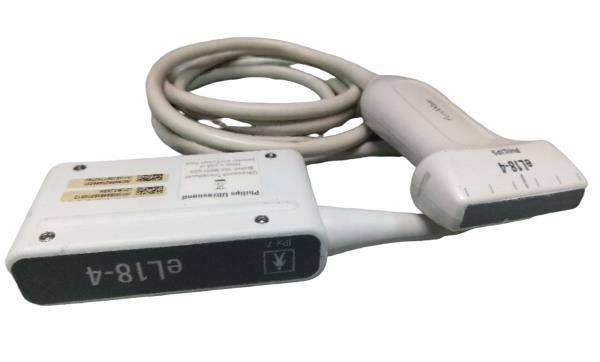

The Laptop Ultrasound scanner integrates cutting-edge technology and high-resolution imaging, making it an essential tool for medical professionals. It features a Transvaginal probe, which allows for detailed examinations of female reproductive organs, ensuring that healthcare providers receive the most accurate information possible. This technology minimizes discomfort and enhances patient care because it offers excellent visualization without needing invasive procedures.